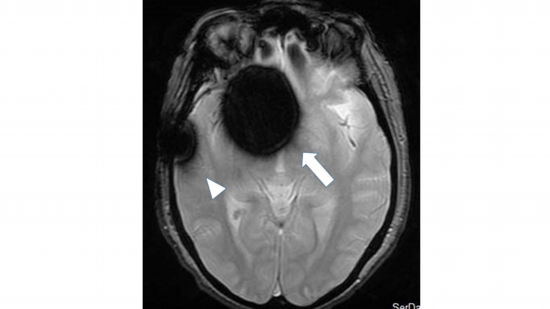

Figure 4

Shows artifacts (signal disturbances) that are a drawback of T2*-weighted images.

After clipping an aneurysm aneurysm, there is a huge spherical low-signal area around the aneurysm clip (arrow), and the titanium cranioplasty plate on the right temporal region exhibits metal artifacts, making the surrounding lesions undiagnosable. (arrowhead).